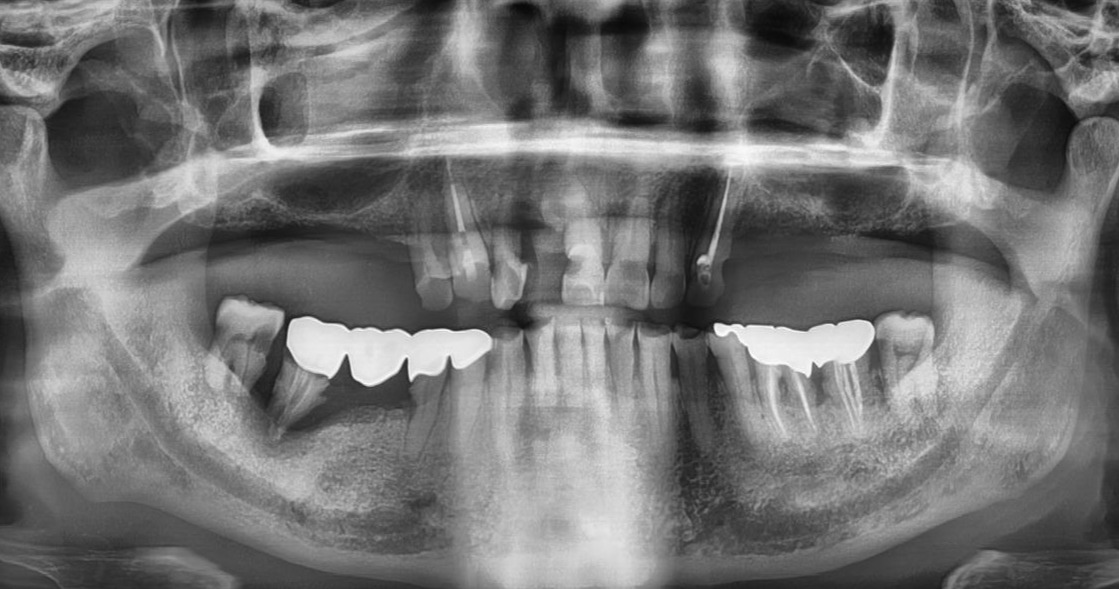

치과의사들은 이런 방사선 파노라마 사진에 익숙하다. 파노라마 사진을 보면 환자의 얼굴이 바로 생각난다.

수십 년간 치과에서 환자를 진료해본 의사라면 공감할 수 있는 것이 있다. 바로 파노라마 사진만 보면 그 환자의 과거가 보인다는 것 말이다. 환자의 얼굴보다 파노라마 사진을 봐야 그 사람이 더 잘 기억난다. 물론 정확하지 않은 경우도 있지만 현 치아 상태는 분명 그 사람의 지난 과거의 성장과정, 생활습관, 경제력, 전신건강, 건강지수, 등을 대략 말해 준다. “현재의 모습은 과거 선택한 것들의 결과물이다.”란 말은 이 상황을 잘 표현해 주는 말이다. 질병 상태에 있는 지금의 모습이 있기까지는, 자신이 선택한 여러 가지 습관들에 문제가 있었다는 것을 의미한다.